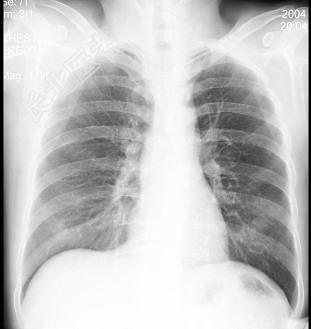

- 单项选择题男性患者,38岁, 突感胸部不适,X线检查如图, 最可能的诊断是 ( )

A、肺部炎症

B、胸腔积液

C、肺结核

D、正常心、肺、膈

E、气胸